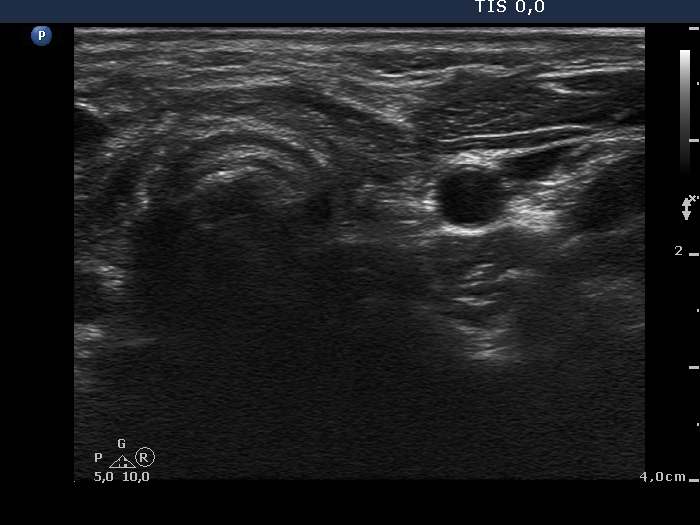

Second examination - one year after surgery (3rd row of images)

Ultrasonography: There was no parenchyma according to the thyroid which was replaced by connective tissue.